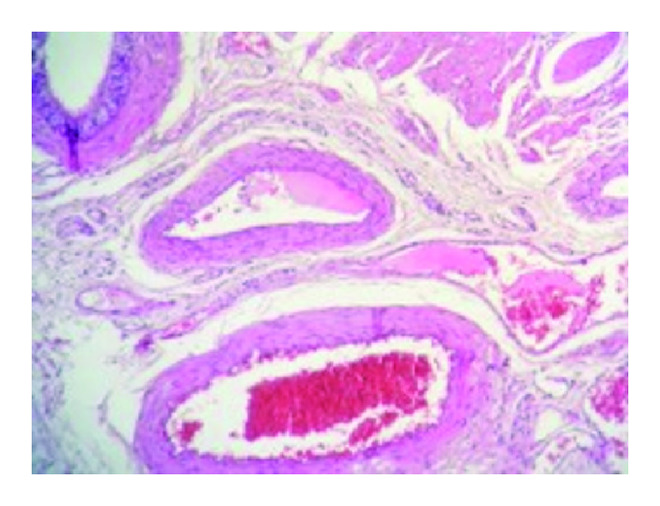

Histological examination concerned a 1276-centimeter orchiectomy specimen. Testicular parenchyma had a normal microscopic aspect. The epididymis caput contained a regular hemorrhagic nodule measuring 55 millimeters. Microscopic examination of the nodule revealed a vascular proliferation made of enlarged vessels, sometimes cystic, separated by an abundant connective tissue (Figures 2(a) and 2(b)). Vascular cavities were congestive and bordered with a single layer of regular endothelial flat cells (Figure 3). The vessel’s wall was thickened, with variable degrees of adventitial fibrosis. The lesions were concordant with the diagnosis of an epididymal cavernous hemangioma.

(a)

(b)